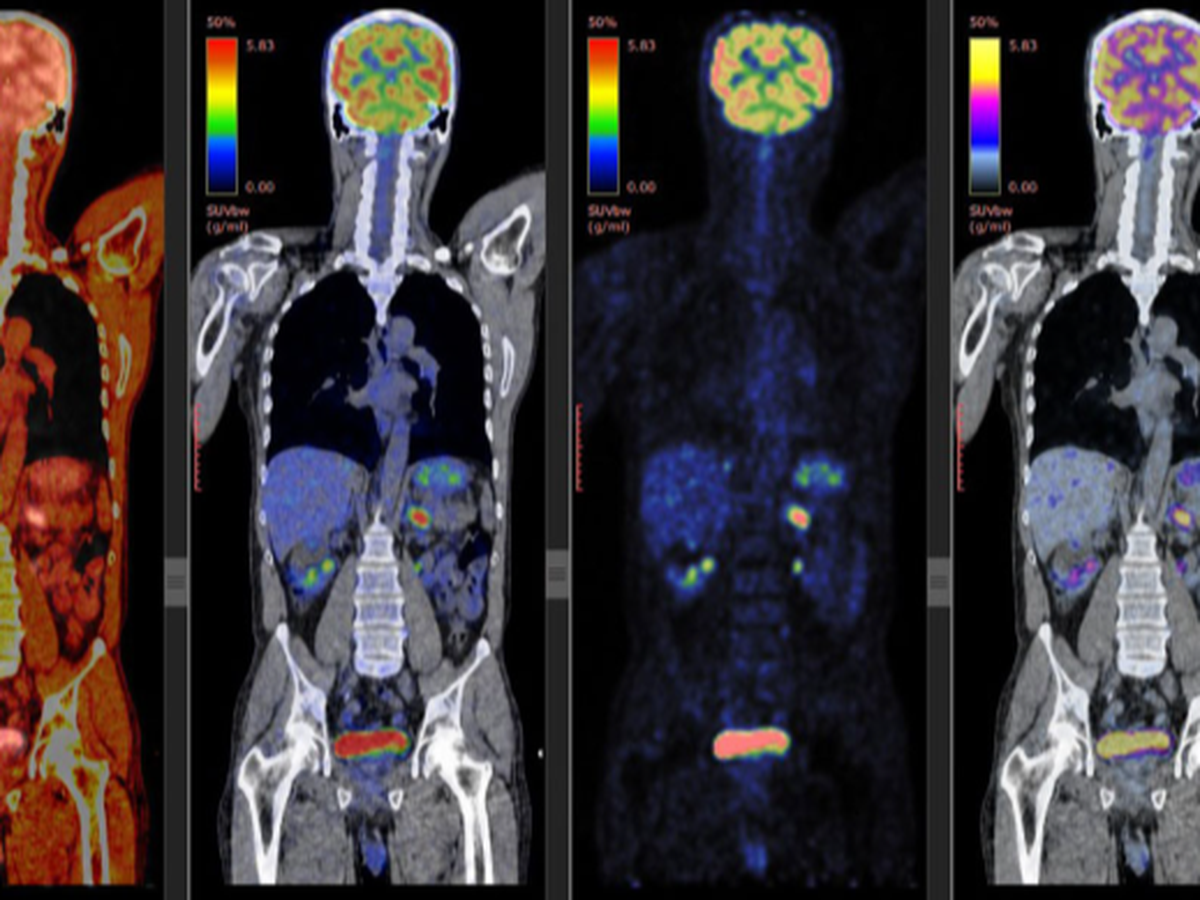

To raise the money needed to get a PET scan.